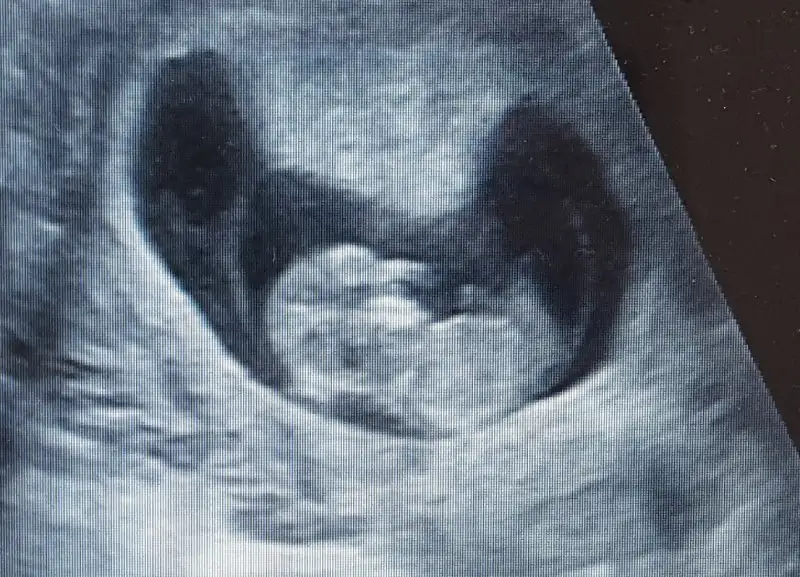

Yenı uyeyım :) 6 haftalık ultrason goruntumuz sızce cınsıyetı ne olabılır?

Eki Görüntüle 2088195 Eki Görüntüle 2088194